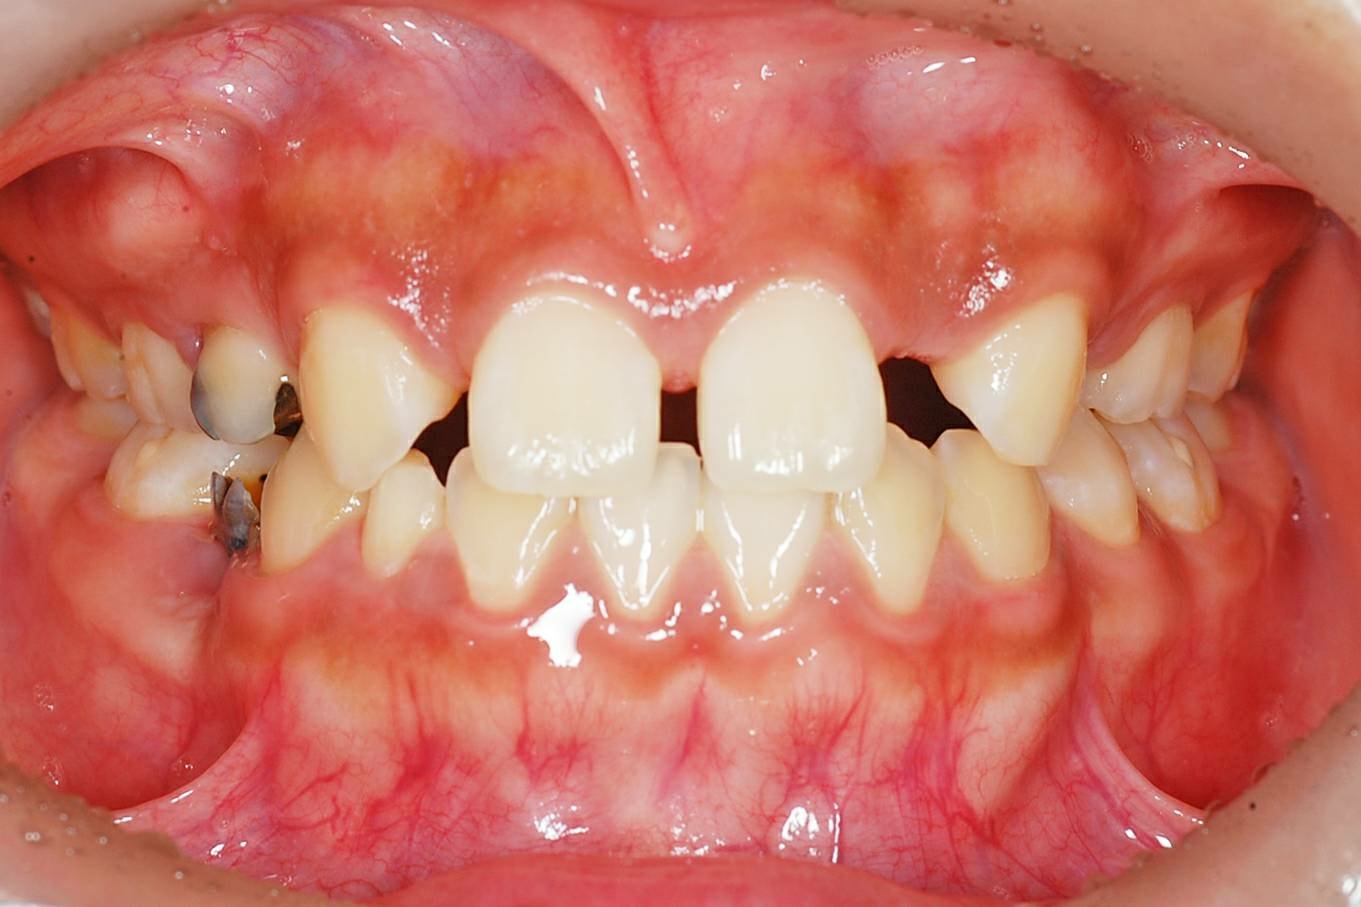

矯正治療で抜歯を行わなくてはならない理由の第1点目は、患者固有の顎が小さいか、歯が大きい場合などの問題です。このような顎骨と歯の大きさの不調和をアーチレングスディスクレパンシーと呼びます。ディスクレパンシーに対してある程度は、歯列や骨の拡大などで対応できますが、限界を超えた場合には、抜歯によりディスクレパンシーを解消することになります。大きなディスクレパンシーを持つ患者さんに対して、非抜歯治療を行った場合、過度な唇側への突出がおこったり、それに伴う唇側歯肉の退縮など歯周組織への悪影響、口唇閉鎖機能不全などの問題を生じる場合があります。また、長期の安定も重要な要因なので、それらも含め、限界を超えたと判断される場合には抜歯の適応症と判断します。

抜歯が必要となる第2点目は、上下顎の骨格的な偏位、臼歯(奥歯)のかみ合わせに偏位が認められる場合です。このような不正咬合は本来、成長発育の不調和に起因するため、根本的には外科的に改善すべきだということになります。しかし、顎骨の不調和が原因であっても、境界領域であれば矯正治療単独での治療方針で改善することができます。その多くの場合には抜歯により咬合を獲得することとなります。

第3の理由は、口唇閉鎖不全(歯が出ていて唇を閉じることができない)による機能的な問題の改善と、軟組織側貌などの審美的改善によるものです。口唇の閉鎖不全は、口腔内が乾燥するため、齲蝕や歯周病などの様々な感染リスクを増大させ、呼吸、発音、嚥下に対しても問題を起こします。また口唇が閉じられずに、いつもお口があいている状態も好ましい状態ではありません。口唇閉鎖不全の多くは、上顎前突や下顎前突、上下顎前突などの、主に歯の位置や骨格的な不正により引き起こされます。このような問題から引き起こされた口唇閉鎖不全は、矯正治療で改善が可能です。